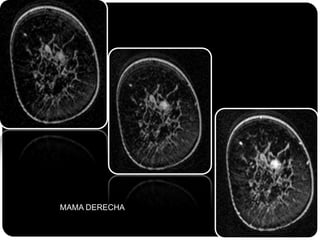

Paciente femenina de 66 años con historia clínica de 1er gesta antes de los 30 años y antecedentes de lactancia positiva, presenta una lesión palpable en la mama derecha. Los estudios radiológicos indican un diagnóstico de bi-rads 5, con biopsias revelando adenocarcinoma lobulillar infiltrante en la glándula mamaria derecha y adenocarcinoma ductal in situ en la izquierda. El caso fue evaluado por las doctoras Jacqueline Preciado Vargas y Beatriz E. González Ulloa.